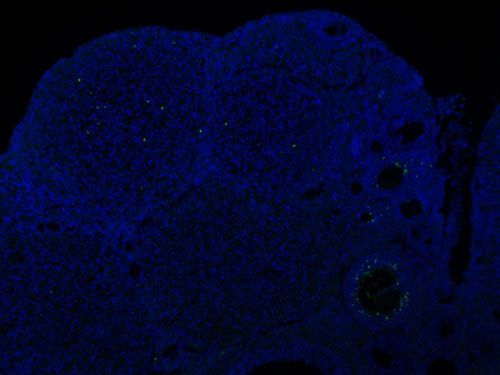

實驗結果展示:

TUNEL(熒光)檢測-小鼠卵巢

TUNEL(熒光)檢測-小鼠腸